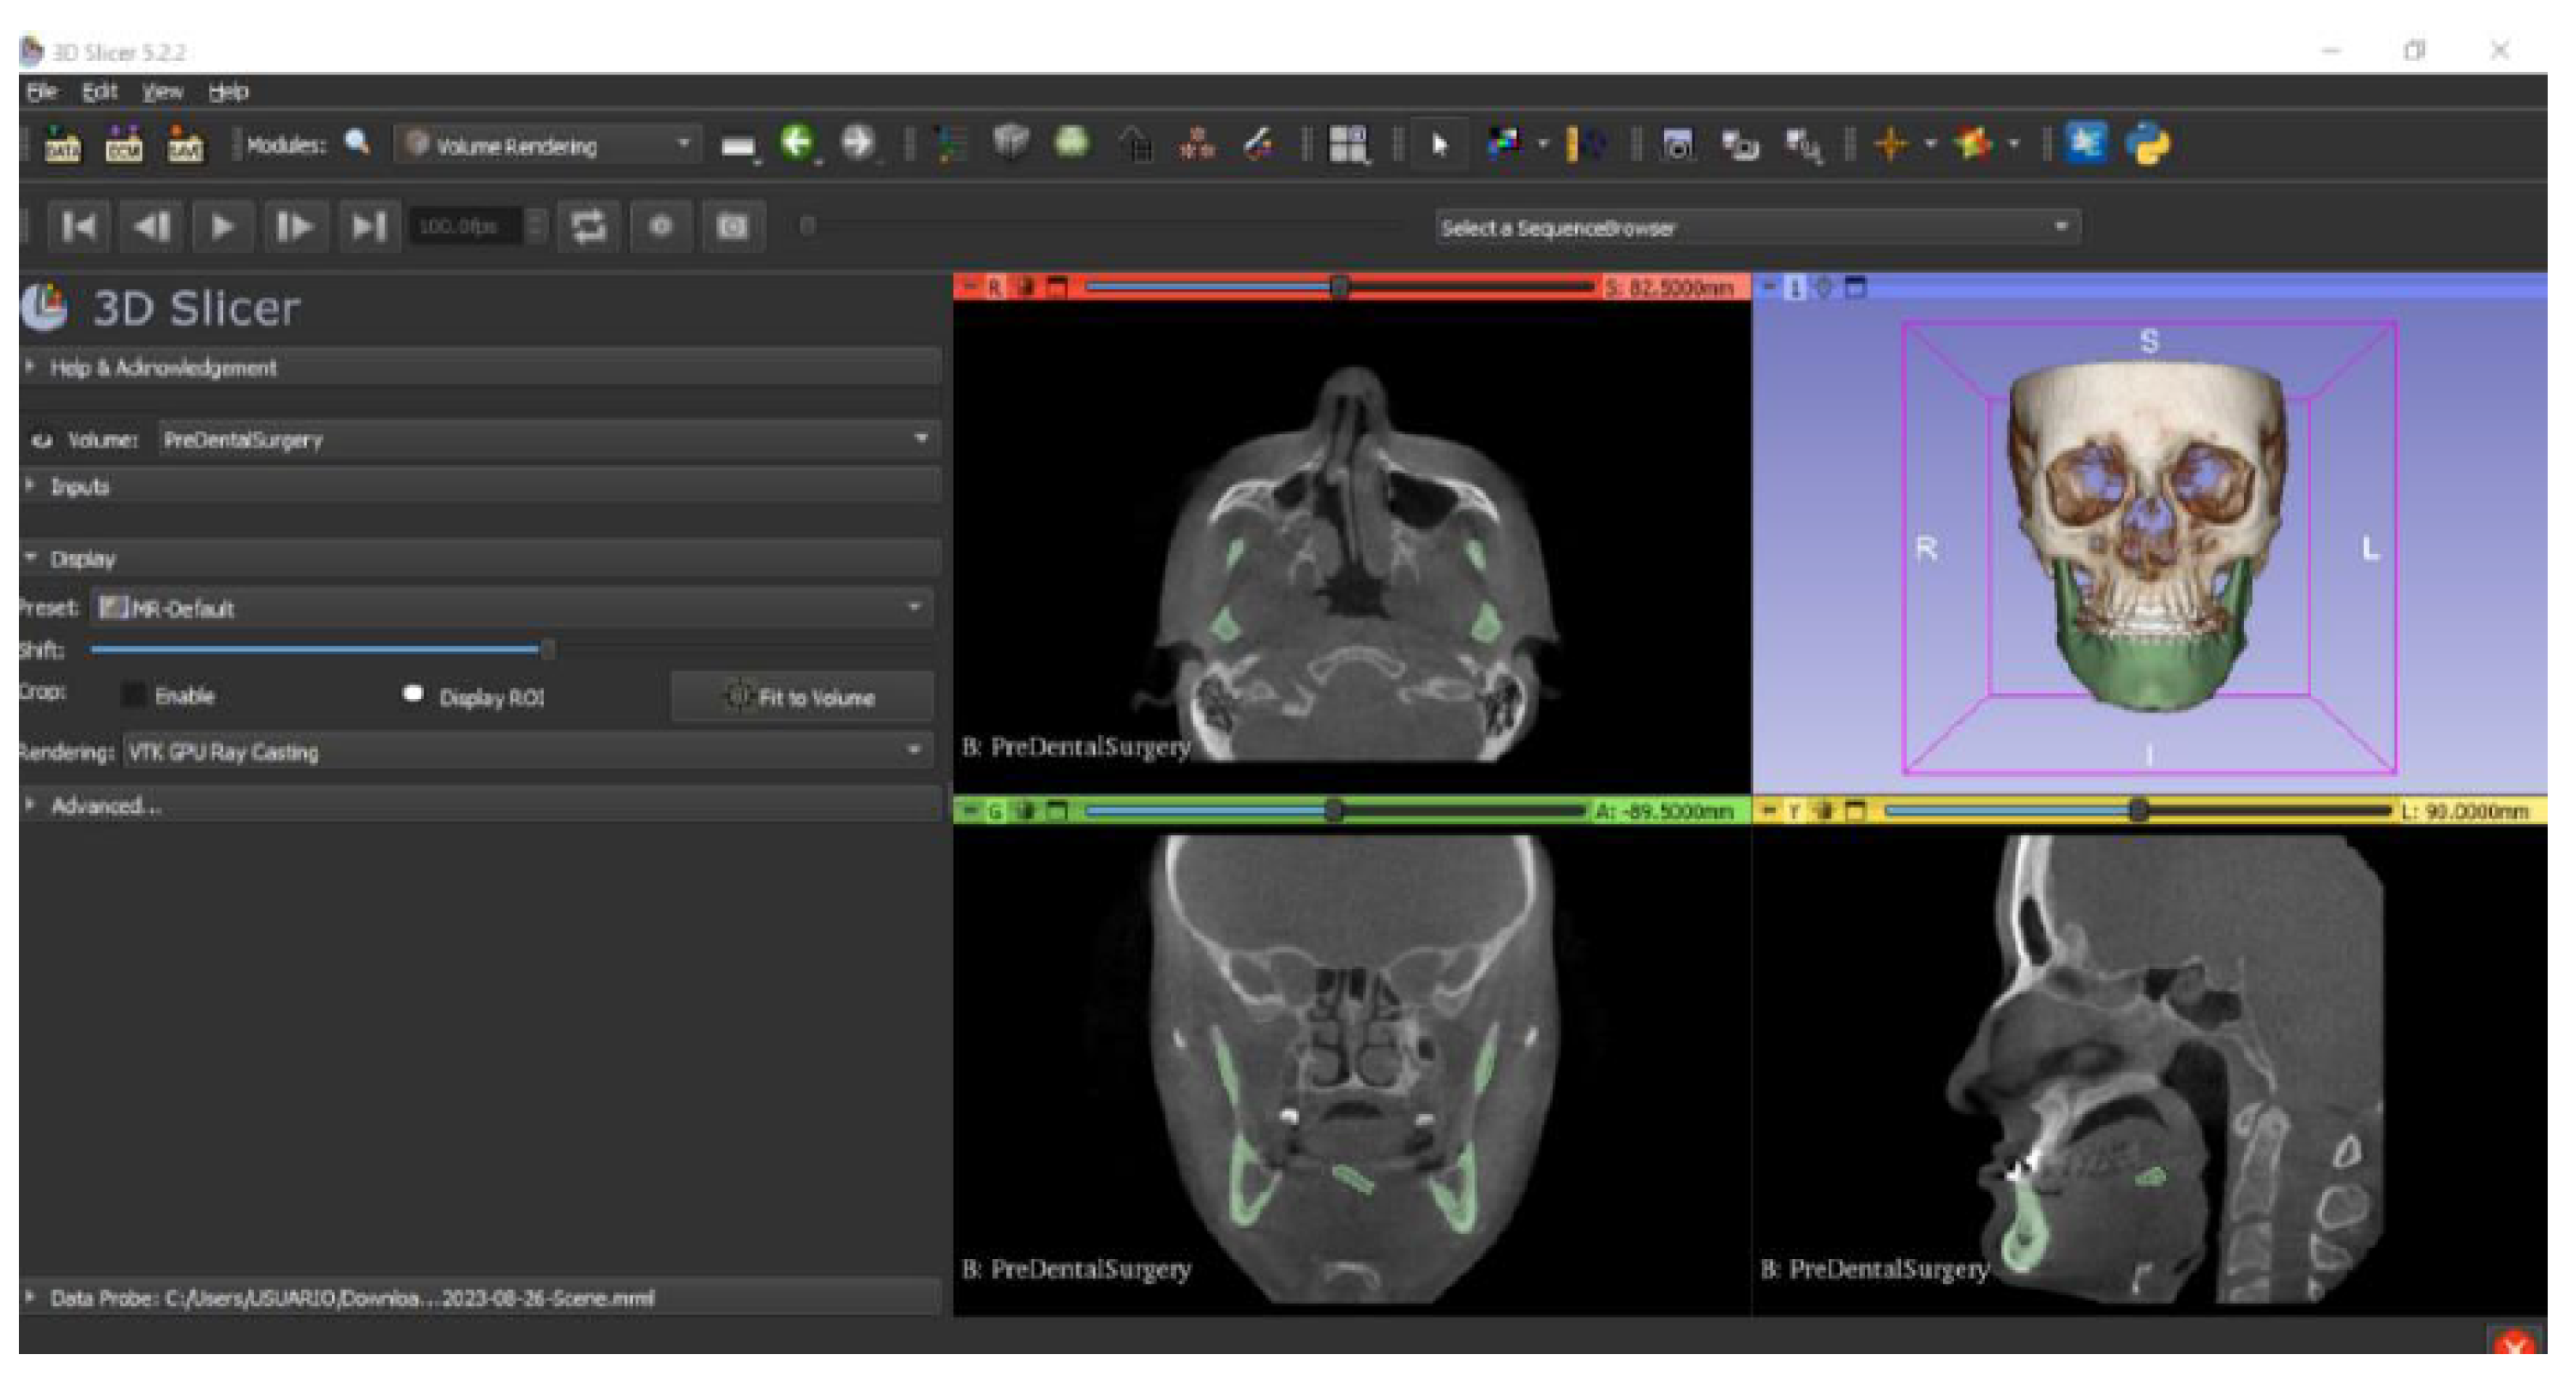

- Go to the “Layout Selection” in the tool bar, and select “Four-Up” view. This configuration allows for the visualisation of DICOM images in three different views, along the 3D view.

- Select the “Volume Rendering” module in the toolbar.

- Select the volume of interest in the drop-down menu, and activate the rendering function.

- Configure the rendering process by accessing the “Display” drop-down. Choose the most appropriate “preset” option in terms of the image and anatomical model tissue.

- Use the Shift function to adjust the rendered visible tissues, and enable the “Crop” option in order to cut the “region of interest”.

- Make the Region of Interest (ROI) display visible in order to visualise it, and adjust the ROI volume rendering square in the region of interest for the 3D view.

3.2.1. DICOM-to-STL Files